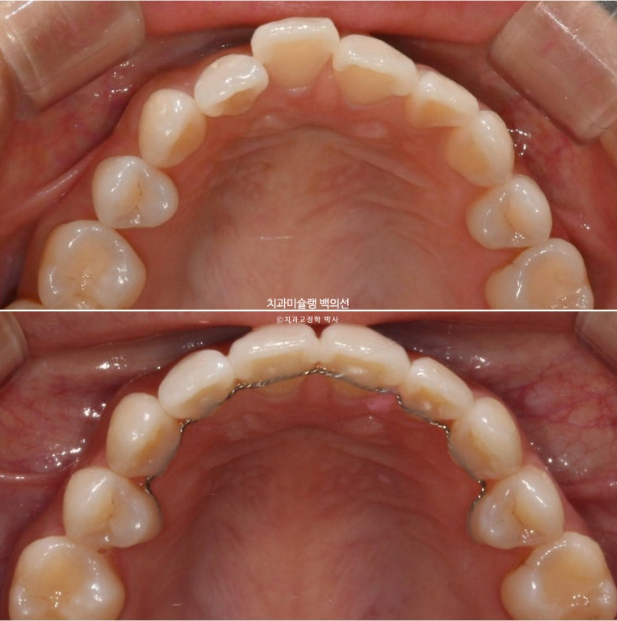

25년 7월부터 9월까지 7개 추가장치를 낀 후 치료를 마무리 했습니다.

25.09

총 치료기간은 6개월이고 재제작은 1회 했습니다.

철사 교정식 유지장치까지 꼼꼼하게 들어갑니다.

이제 전 후 비교 보겠습니다.

25.03~25.09

깔끔해진 미소가 돋보입니다.